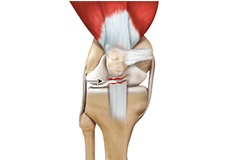

Ligament Injuries

The knee is a complex joint that consists of bone, cartilage, ligaments, and tendons that help in your joint’s movements. The knee is a hinge joint made up of two bones, the thighbone (femur) and shinbone (tibia).